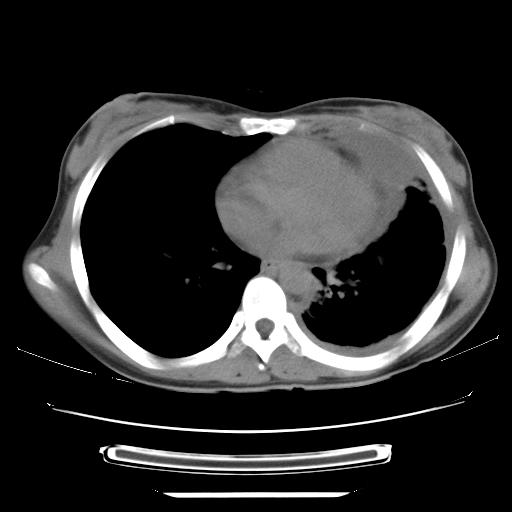

女,29岁,胸部不适,在外院胸片提示胸腔积液,到我院ct检查。

纵膈窗

左肺上叶不张,左侧胸水,叶间裂积液,纵隔淋巴结,脾脏钙化,考虑左肺上叶支气管内膜结核,结核性胸膜炎,脾结核

支持两肺继发性肺结核,左侧胸膜腔包裹性积液、胸膜肥厚,脾内多发钙化(结核钙化)。

右肺多发结节。左胸腔多发包裹性积液。